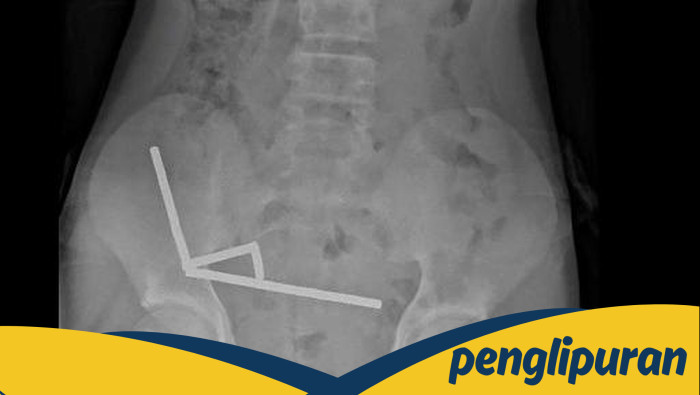

Seorang anak laki-laki berusia 13 tahun di Selandia Baru baru-baru ini mengalami insiden menakutkan setelah menelan lebih dari 80 magnet neodymium. Kasus ini tercatat dalam laporan terbaru di New Zealand Medical Journal, yang menguraikan risiko serius dari menelan benda-benda kecil seperti magnet berkekuatan tinggi. Anak tersebut harus menjalani operasi紧急 karena komplikasi yang ditimbulkan oleh tarikan magnet yang kuat, yang menyebabkan bagian ususnya saling menempel dan terjadi perforasi.

Magnet neodymium, meskipun sering dijual sebagai mainan untuk orang dewasa, memiliki risiko tinggi jika tertelan. Ukurannya yang kecil membuatnya mudah dikonsumsi oleh anak-anak, namun efeknya bisa fatal. Tarikan magnet yang kuat dapat menyebabkan bagian saluran pencernaan menempel, menyebabkan nekrosis akibat tekanan, perforasi usus, atau infeksi serius yang mengancam jiwa. Kasus ini menjadi pengingat penting tentang pentingnya mengamankan benda-benda berbahaya dari jangkauan anak-anak.

Studi menunjukkan bahwa magnet neodymium, dengan daya tarik yang jauh lebih kuat daripada magnet biasa, dapat menyebabkan kerusakan serius pada saluran pencernaan. Jika lebih dari satu magnet tertelan, risiko komplikasi seperti usus robek atau infeksi meningkat secara signifikan. Para ahli merekomendasikan untuk segera memeriksakan diri ke rumah sakit jika ada dugaan bahwa magnet atau benda-benda kecil lainnya telah tertelan.